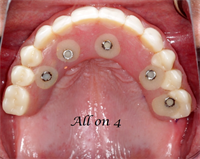

Which Parts Do I Need for "All on 4" Style Cases?

Don't get stuck without the parts you need. For new providers getting into "All on 4" style cases, get organized and have your parts ready ahead of time so there is no scrambling. This brief video outlines what you need to be successful! Enjoy!! ...  Read More